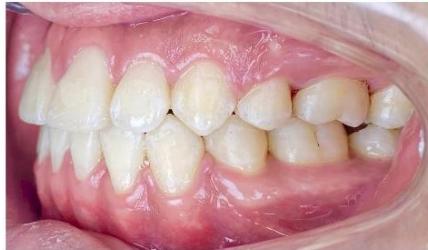

### b) Intraoral Examination

Intraoral examination revealed severe proclination and protrusion of both the maxillary and mandibular incisors [6]. The occlusal relationship was Class I at the canine (tooth 3) and first molar (tooth 6) levels bilaterally. A critical unfavorable biological factor was the proximity of the mandibular incisor roots to the labial cortical plate, representing a high-risk condition when planning extraction-based anterior retraction mechanics [10-12]. All four third molars were present.

Figure 2: Pre-Treatment Intraoral Photographs